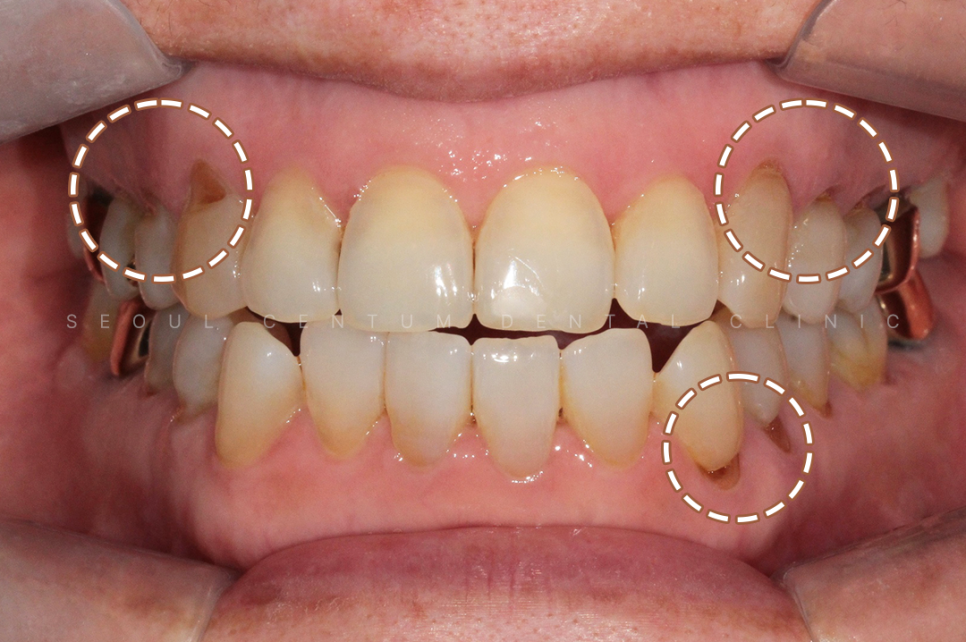

실제 육안으로 봤을 때도 크게

치경부마모증이 진행된 부분이 많았고

당일에 바로 진행을 하게 되었습니다.

크게 진행이 된 8개의 치아를 진행하기로 했고

강도가 강한 레진으로 진행해 오래

유지를 잘 해보시기로 이야기가 되어

레진으로 진행을 했습니다.